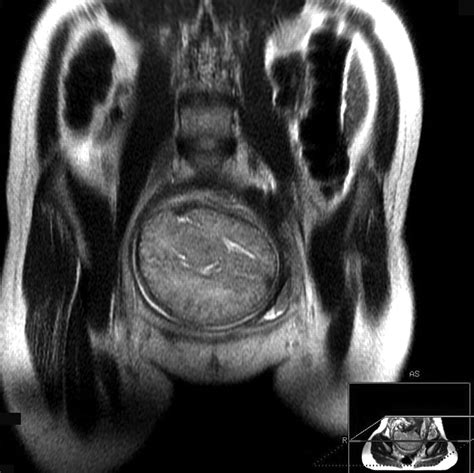

The biparietal diameter is the distance between the two parietal bones of the fetal skull. It is measured during an ultrasound examination, typically between 18 and 22 weeks of gestation. This measurement is essential for estimating the gestational age of the fetus and monitoring its growth. The BPD is one of several parameters used to calculate the estimated fetal weight and to ensure that the baby is developing normally.

• Measurement: The technician identifies the fetal skull and measures the distance between the two parietal bones. This measurement is recorded and compared to standard charts to determine the gestational age and growth parameters.